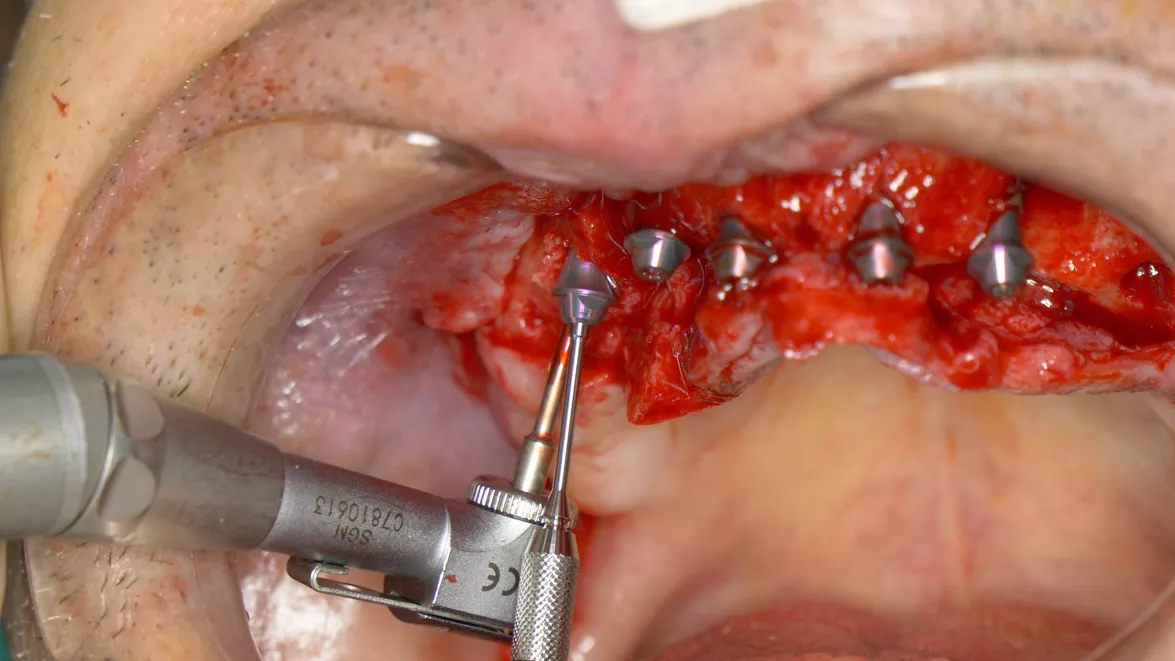

• Placement of the Screw-retained Abutments (courtesy of M. Laureti and N. Ferrigno).

Rounded and slim angulated abutments maximize the space for soft tissue. Efficient: the single connection system reduces the number of abutments while keeping all clinical options open. The SRA should be tightened with 35 Ncm – like all BLX final abutments.